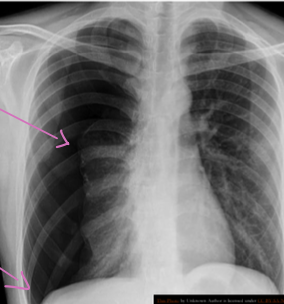

A 32 years old male presented with history of low grade fever, cough with sputum, sometimes blood stained. He has weight loss of 5 kg during this period. His chest X-Ray is shown ABOVE.

Describe the abnormality seen in the X-Ray?

- Cavitation and consolidation in the left upper lung

- bilateral Hilary lymphadenopathy

What is the likely diagnosis? Pulmonary TB

Mention 2 other investigations which you will advise?

- o Sputum culture and smear

- o IGRA

Mention 2 factors which increase the risk of this disease?

- HIV

- Chemotherapy

Mention 2 drugs used to treat this medical condition?

- o Rifampicin

- o INH (Isoniazid)